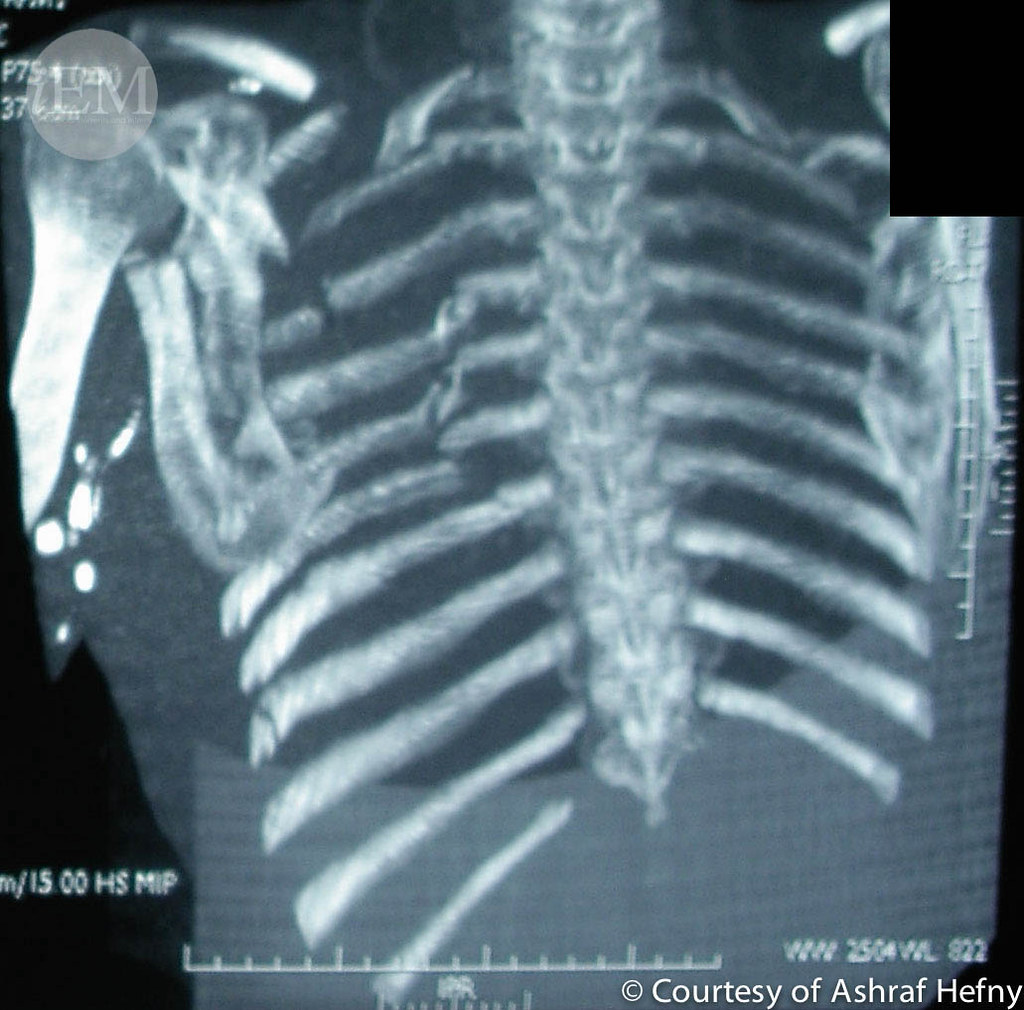

From www.flickr.com

7 Flail chest case 4 Emergency Medicine Clinical Images and Videos Emt Flail Chest Treatment This may be sufficient for small flail segments, which don’t compromise breathing mechanics. Surgical repair of flail chest has been shown to reduce rates of pneumonia, permanent chest deformity, and mortality. Also shown to reduce the need for tracheostomy,. Explore the critical aspects of emt management for chest injuries, including the diagnosis, treatment, and prehospital care strategies for conditions like. Emt Flail Chest Treatment.